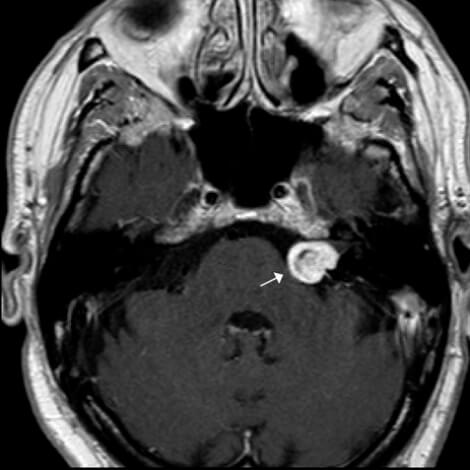

Figure 1. Contrast-enhanced axial T1WI magnetic resonance imaging (MRI) showing

a left-sided CPA lesion (arrow) compatible with a vestibular schwannoma.